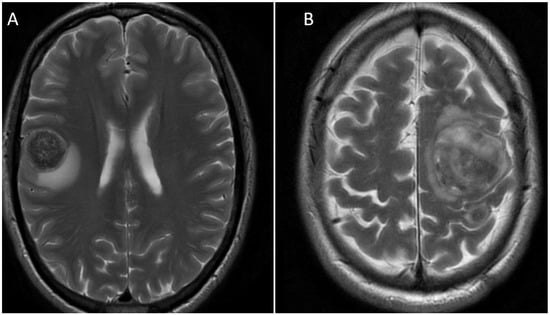

| 52-year-old, Male | GOJ, local nodal disease, brain metastasis. | Nil, de novo presentation. | Left facial weakness and lower limb sensory changes. | Right parietal lesion. | Stereotactic craniotomy and debulking surgery. Post-operative radiotherapy. | Palliative radiotherapy to GOJ primary. Keynote-811 trial a. | 902 days, remains alive at time of data cut off |

| Asymptomatic. | Left cerebellar metastasis (6 months post-initial lesion). | Stereotactic craniotomy and debulking surgery. Post-operative radiotherapy. | Continued Keynote-811 trial beyond progression, with addition of Trastuzumab. Phase 1 trial b. Integrate IIB clinical trial c. | 516 days. remains alive at time of data cut off | |||

| 50-year-old, Male | GOJ, local nodal disease, brain metastasis. | Nil, de novo presentation. | Focal seizure, right arm weakness, Expressive dysphasia. | Left frontal, left temporal, right frontal (total 8 lesions). | Excision and biopsy of largest lesion in left frontal. Whole-brain radiotherapy subsequently. | Trastuzumab/Cisplatin/Capecitabine. Palliative radiotherapy to primary. Stereotactic radiotherapy to the left frontal brain lesion on progression. Stereotactic craniotomy and resection of left frontal and parietal lesions. Nil further systemic treatments. | 660 days |